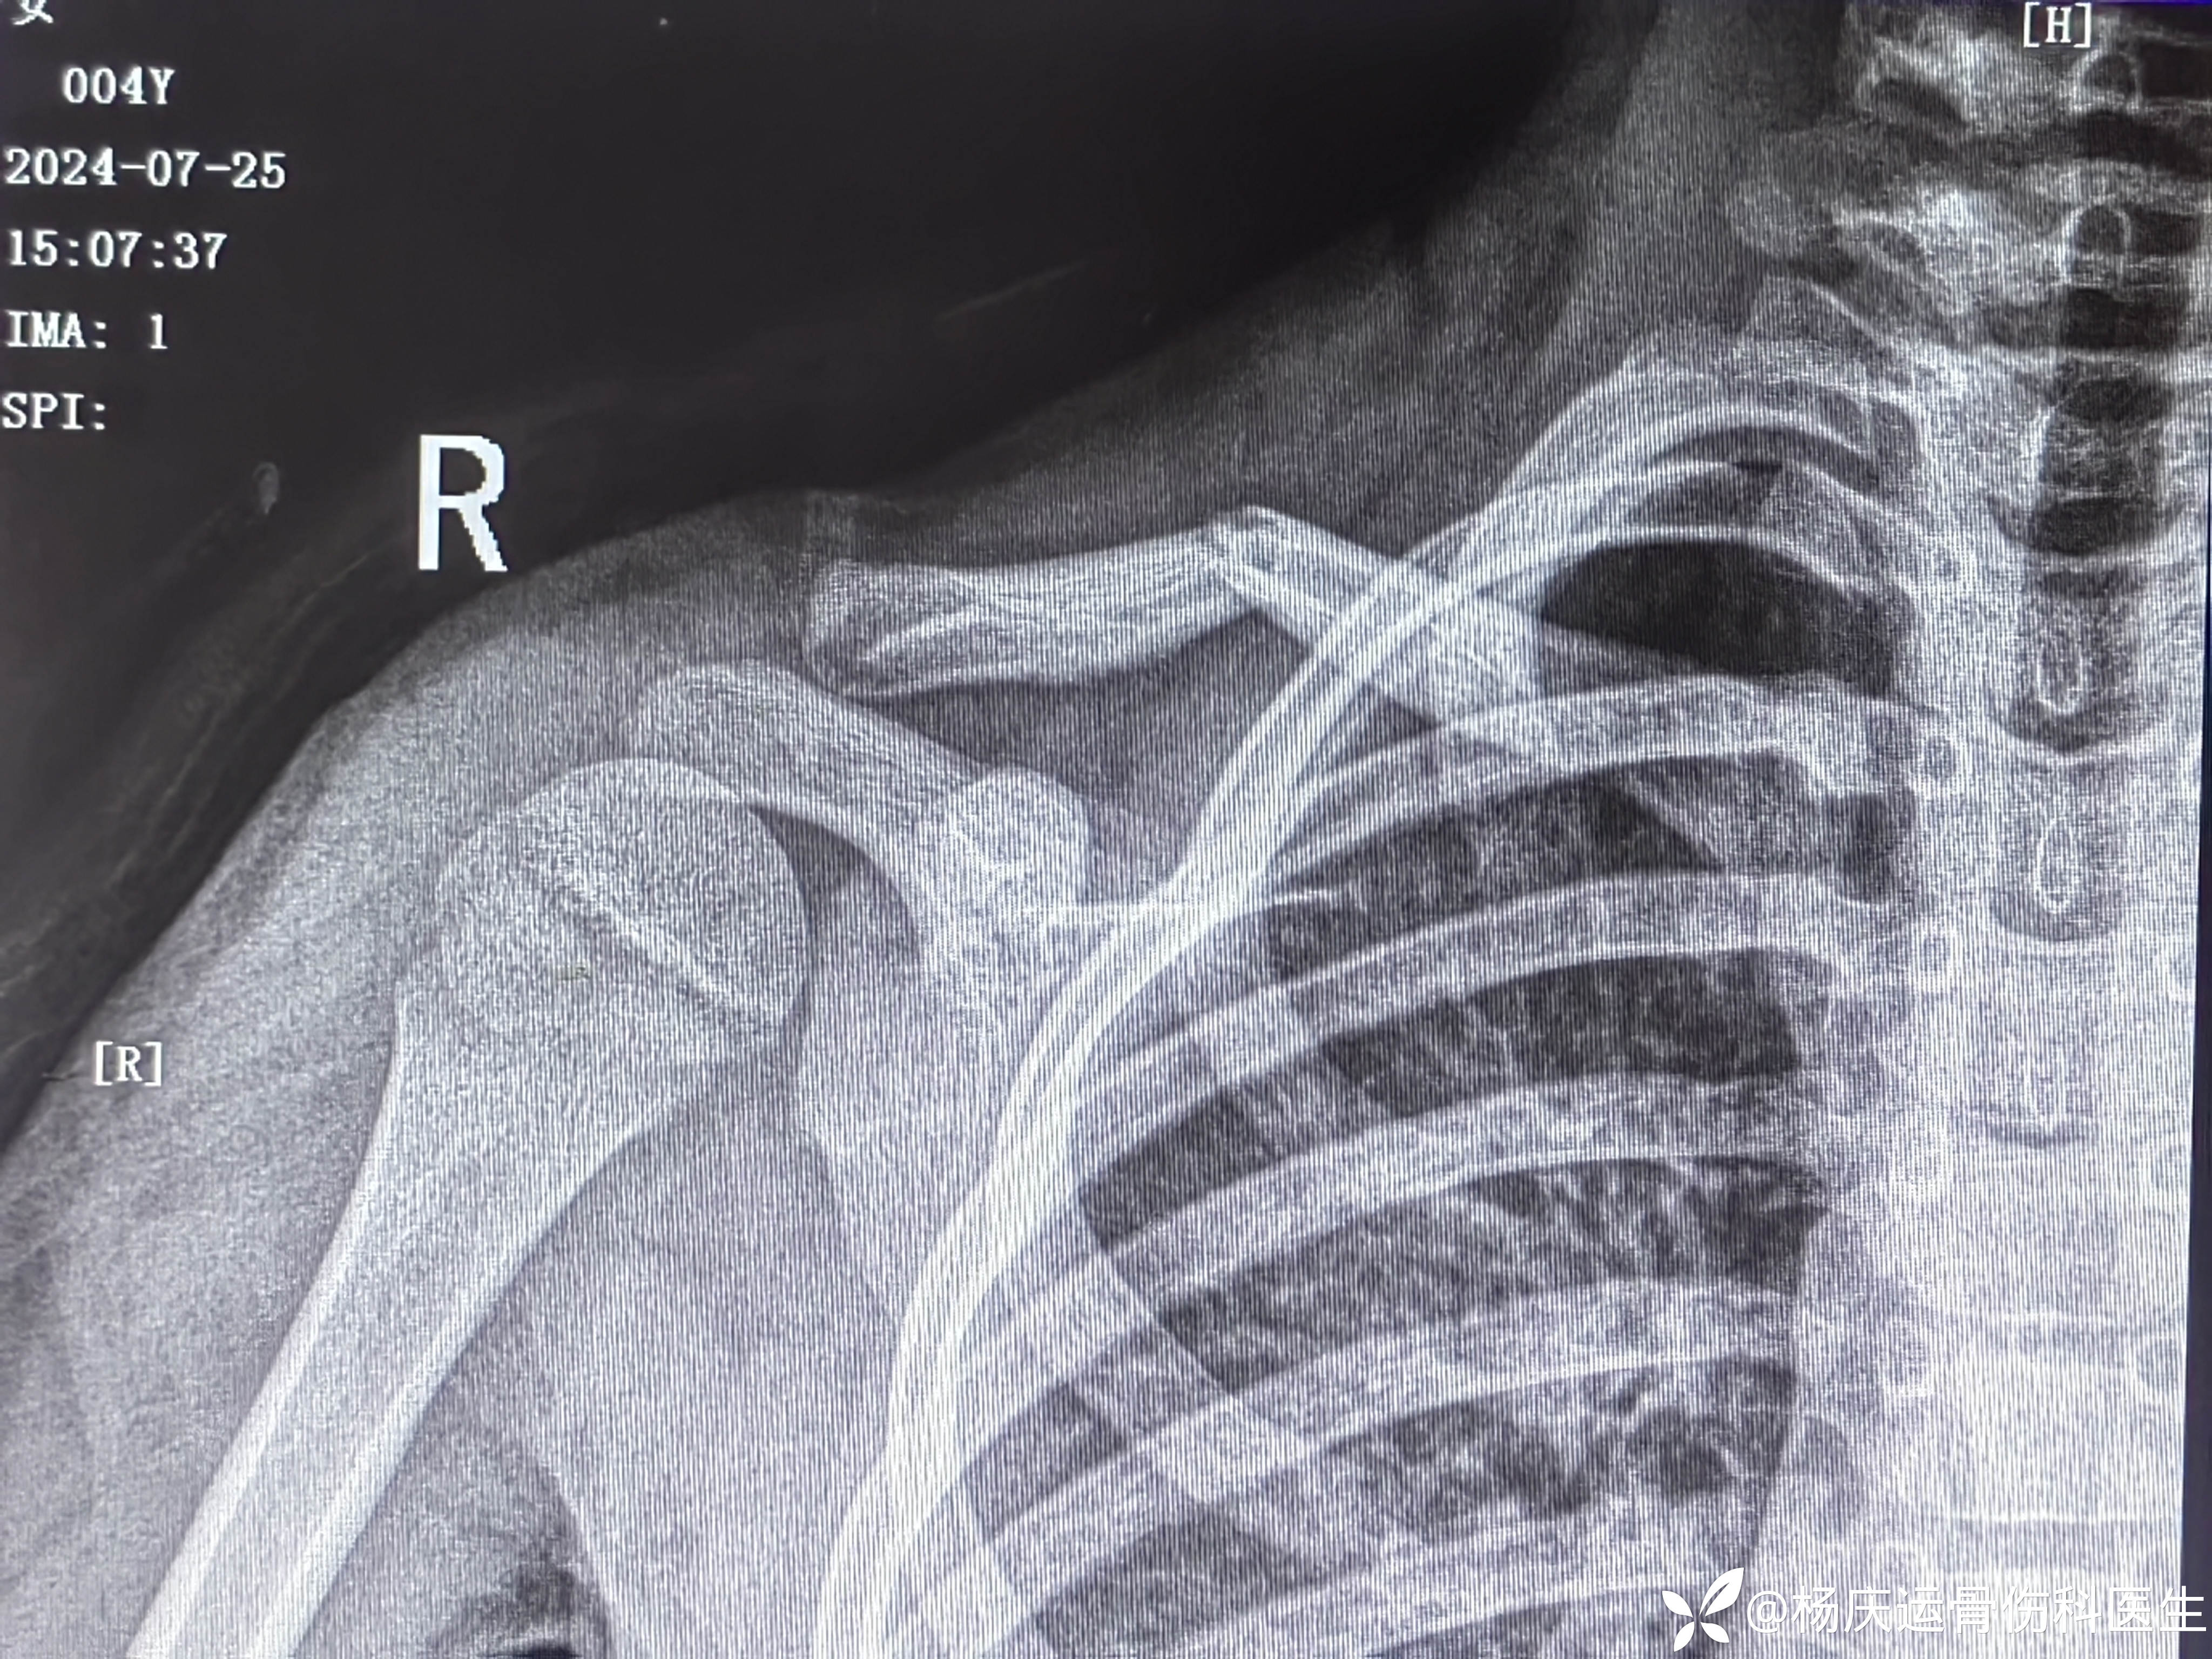

8字绷带外固定后,患者有明显的不适感,且家属对骨折位置不满意。